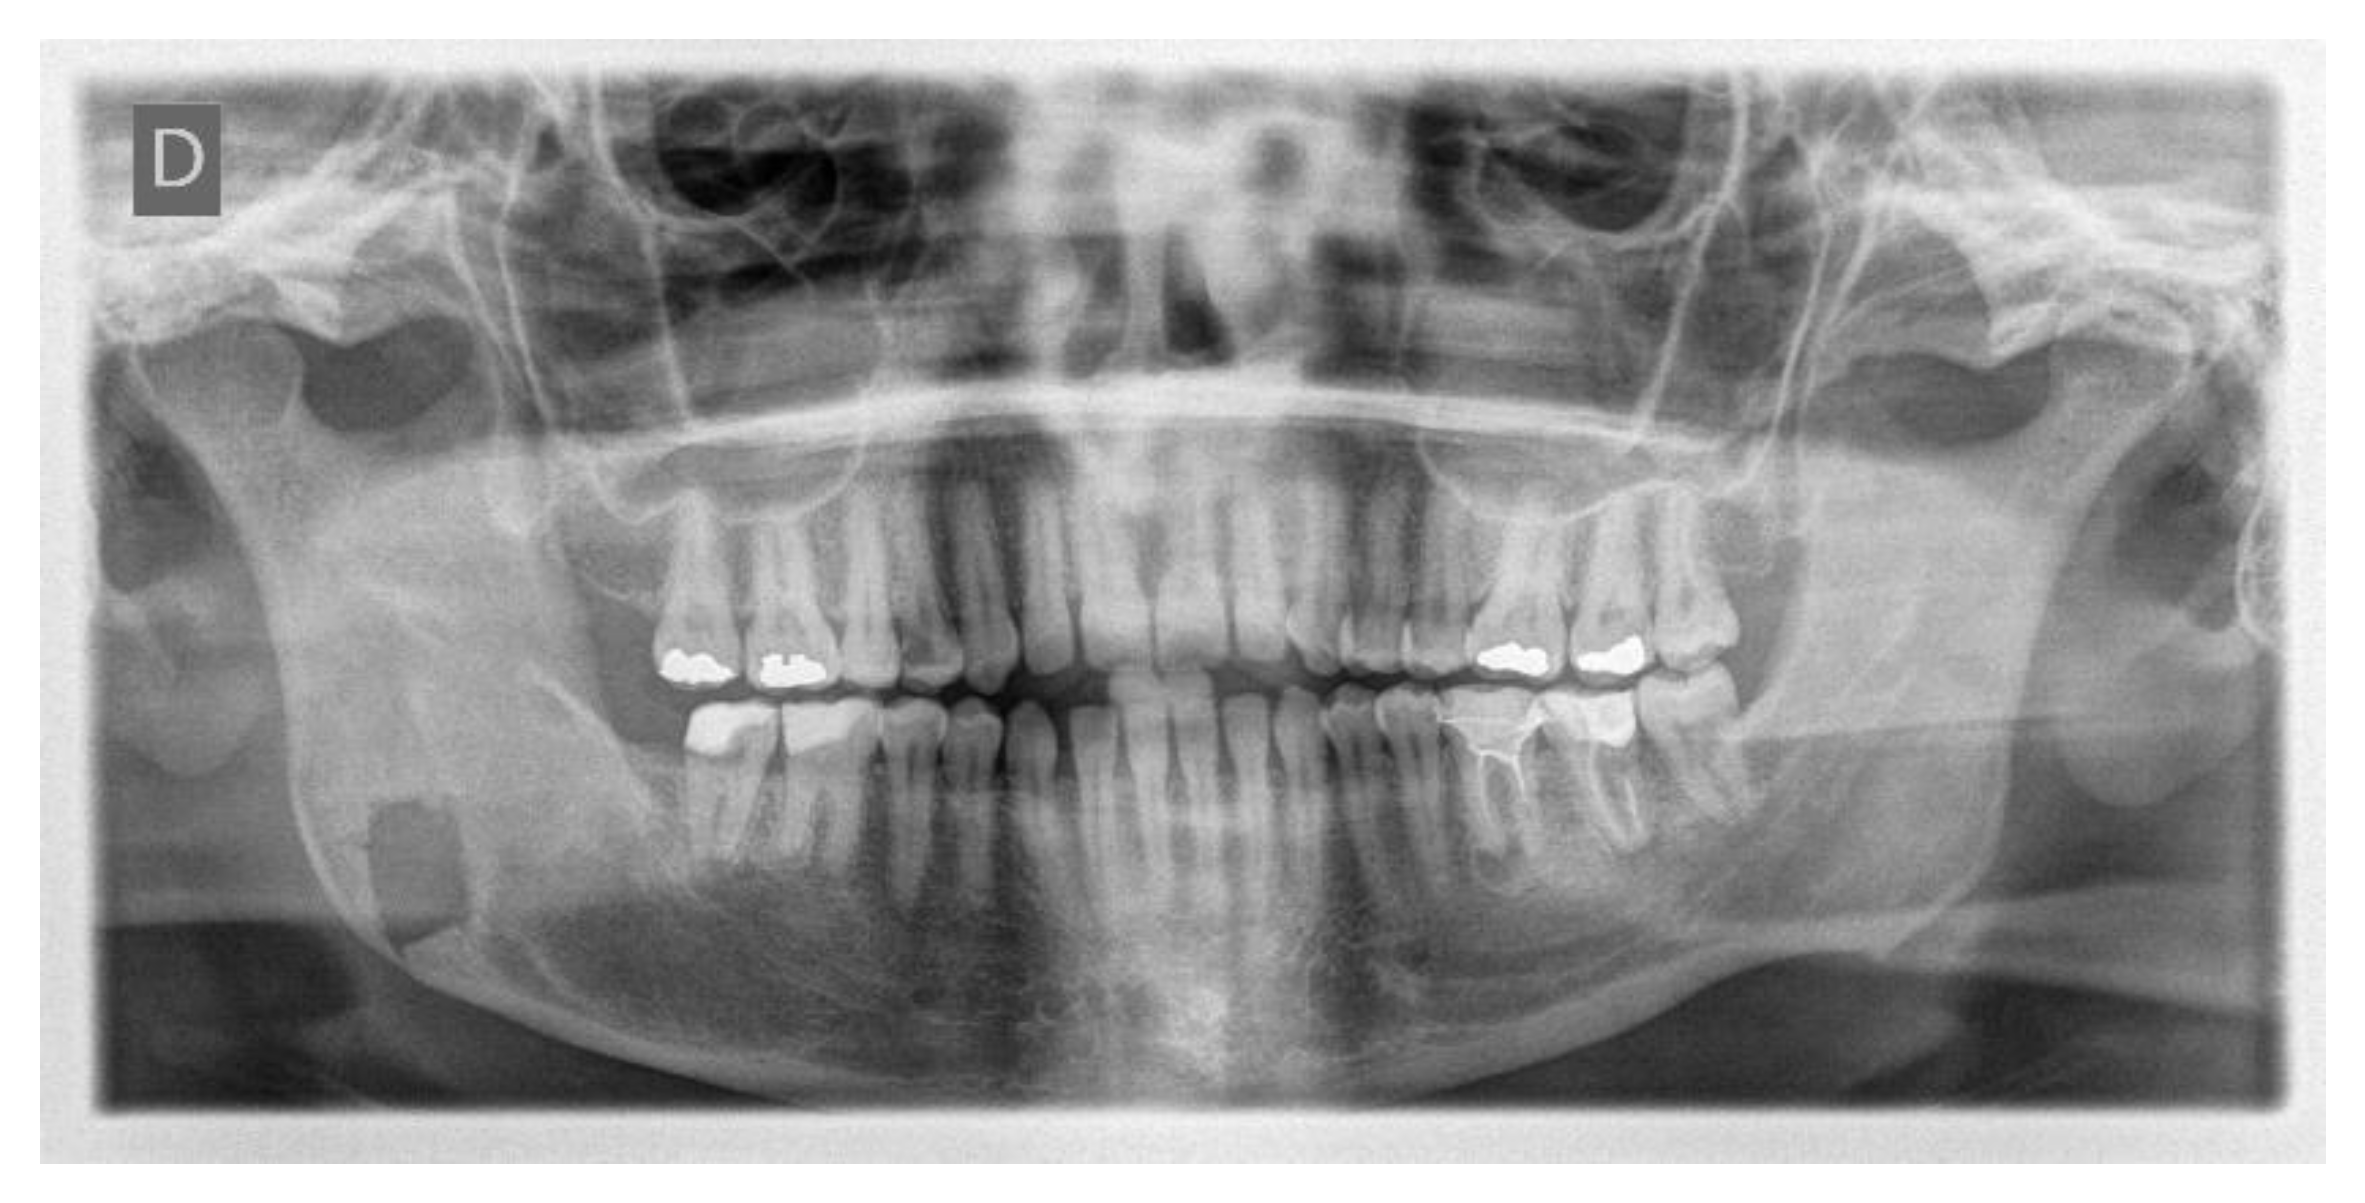

One week post-op, an OPT (Orthopantomography) X-ray was performed, which showed the adequacy of the osteotomy and the preservation of dental roots. Three years later, at the end of orthodontic alignment, the second surgical step was carried out (Figure 11a,b).

Figure 11.

(a) Postoperative Orthopantomography X-ray; (b) post orthodontic alignment.

The day following the surgery, a follow-up OPT X-ray was requested, which displayed the resection area and the integrity of the lower and upper borders of the mandible, in accordance with the preoperative virtual planning (Figure 15).

Figure 15.

Postoperative OPT X-ray showing the resection area and the integrity of the lower and upper borders of the mandible.